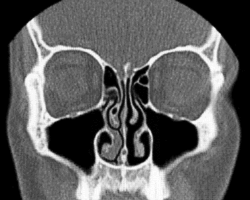

- Normal Nose CT Front cross section

- Coronal section of nasal cavities